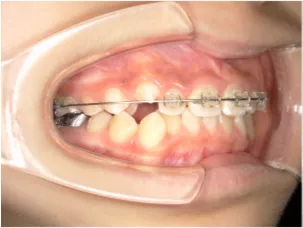

治療前①小5:生え変わり後期のため顔の成長を促進させる目的で拡大装置(アーチ形態の修正)と上顎前歯をそろえることを先行し、できるだけ非抜歯治療で進める予定を提案しました

治療中➁小6:QH・BHでアーチ形態改善・上顎前歯を並べる